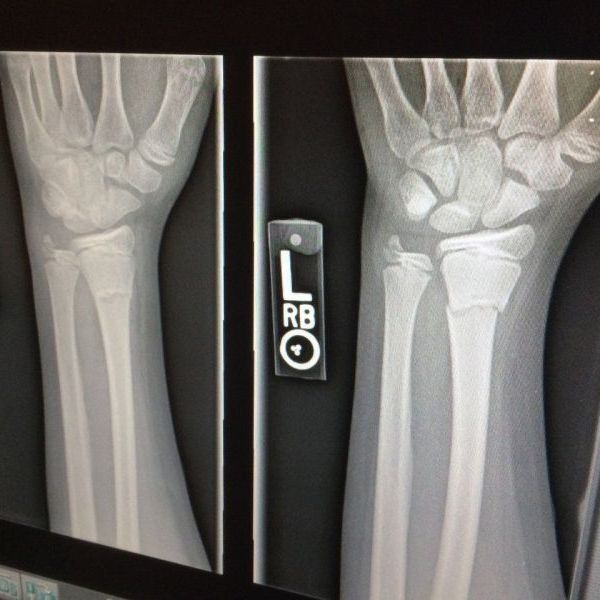

Kórházi látlelet - Törtek a csontok a mai ónos eső miatt Egerben is

Telt ház volt az egri kórház ügyeletén. Számos helyen okozott fennakadást az ónos eső Egerben és a környéken. A gyorsforga...